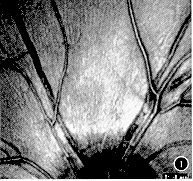

由具有相当经验的研究者判断视网膜神经纤维层状况,分为4种类型:(1)正常视网膜神经纤维层,表现为与视乳头相连的细条索放射状结构(图1)。(2)局灶性缺损或楔形缺损,表现为与视乳头相连的楔形的反光减弱区(图2)。(3)弥漫型缺损,表现为大片的神经纤维层的变薄、发暗,视网膜下小血管清晰可辨,尤其是视乳头上、下血管弓区(图3)。(4)裂隙状缺损,表现为与视乳头相连的裂隙状的暗区(图4)。

图3 视网膜神经纤维层弥漫型缺损